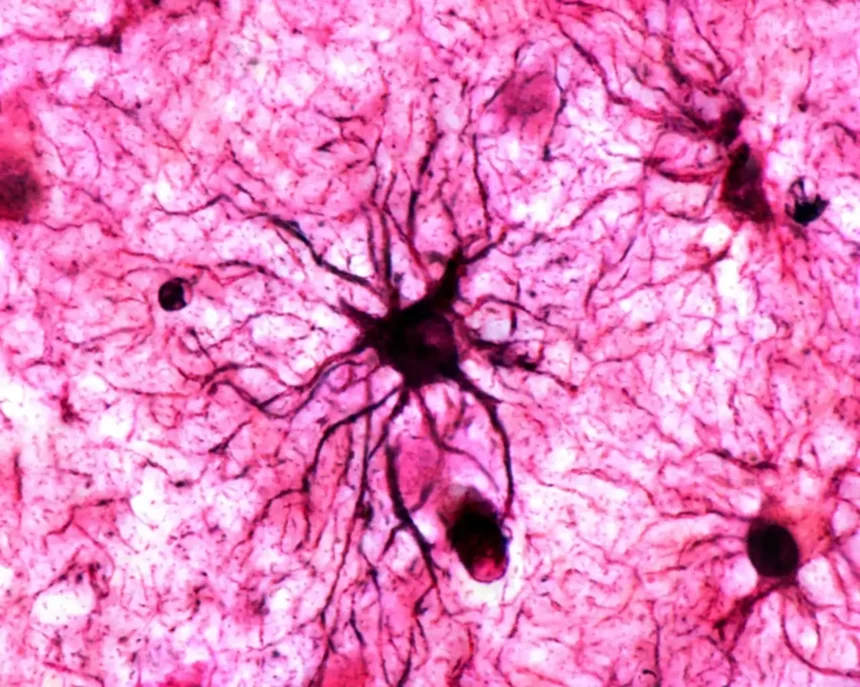

Durante mucho tiempo, los neurocientíficos vieron las astrocitos (esas células en forma de estrella que abundan en el cerebro) como actores secundarios en el gran teatro de la memoria. Encargadas de sostener y nutrir a las neuronas, parecían cumplir una labor casi doméstica dentro del sistema nervioso.

Sin embargo, un estudio reciente publicado en Nature acaba de sacudir esta visión tradicional: las astrocitos no solo participan activamente en el proceso de memorización, sino que podrían ser las verdaderas guardianas de los recuerdos que dejan una huella emocional profunda.

La investigación, liderada por Jun Nagai en el RIKEN Center for Brain Science de Japón, demuestra que estas células gliales no se limitan a acompañar a las neuronas, sino que son capaces de activarse directamente ante estímulos emocionales repetidos, jugando un papel esencial en la estabilización de recuerdos duraderos.